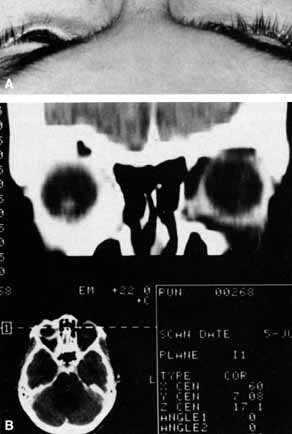

Anosmia caused by damage of cranial nerve I may be a helpful symptom of ethmoid or sphenoid sinus tumors invading the orbit (Fig. 20).44 Olfactory groove meningiomas and esthesioneuroblastomas may also present with anosmia prior to developing vision loss.45 Trauma that involves the orbit and is associated with anosmia should be considered a basilar skull fracture with potential for cerebrospinal fluid leak until proven otherwise (Fig. 21).

Fig. 20 A 13-year-old child presented with a 2-week history of sinusitis and anosmia. Her visual acuity decreased to to 20/400 1 day prior to admission. Computed tomography shows a large ethmoid tumor extending through the cribriform plate and optic canal. A rhabdomyosarcoma was diagnosed by biopsy.